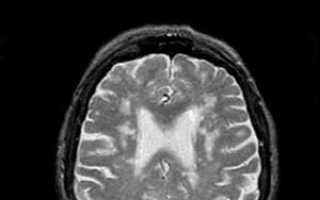

Диагностика

Для установления диагноза «лейкоэнцефалопатия» специалист проведет всестороннее обследование. В этом процессе потребуются:

- магнитно-резонансная и компьютерная томография, которые помогут выявить патологические изменения в головном мозге;